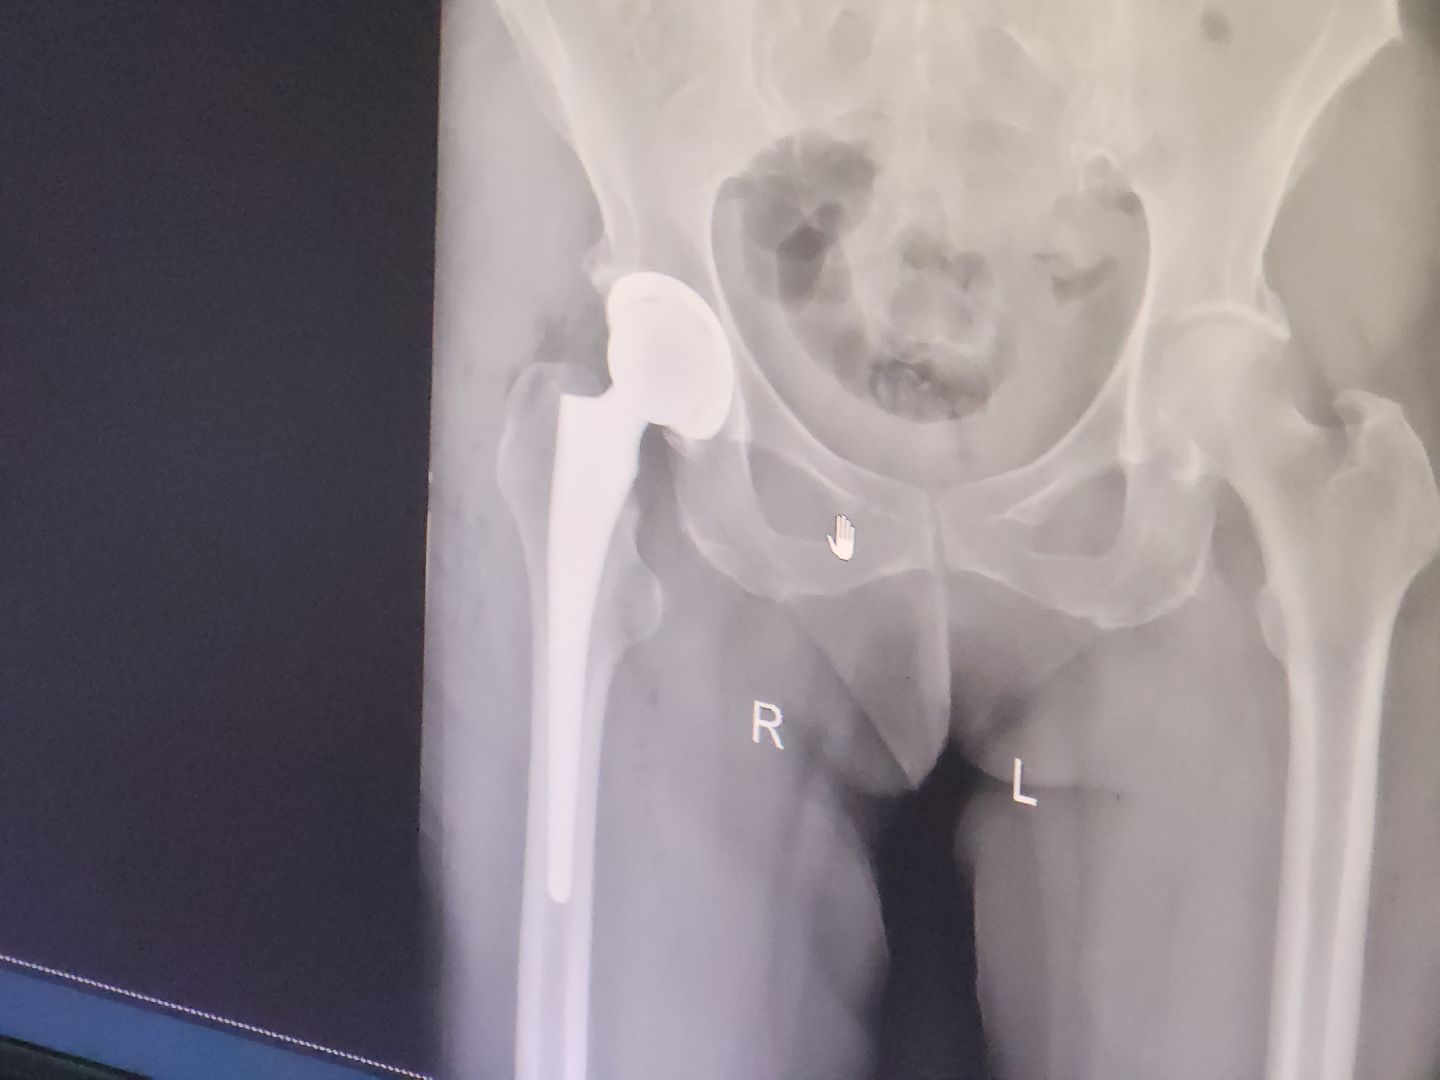

Сегодня молодые хирурги травматологического отделения Красногорской больницы провели успешную операцию на бедре 94-летнему пациенту. Сейчас он уже находится в общей палате. За этот месяц было проведено более 40 операций по ортопедическому профилю. После долгого перерыва в среду в отделении запланированы первые операции по протезированию коленных суставов.

Все необходимые материалы и эндопротезы в наличии. Как утверждает врач, качество имеющихся материалов не только не уступает аналогичным в других клиниках Подмосковья, в том числе и частных, но и в некоторых аспектах превосходит их.

Продолжительность реабилитации после операции зависит от состояния пациента, его возраста и типа эндопротеза. В среднем этот период занимает от 1,5 до 3 месяцев.